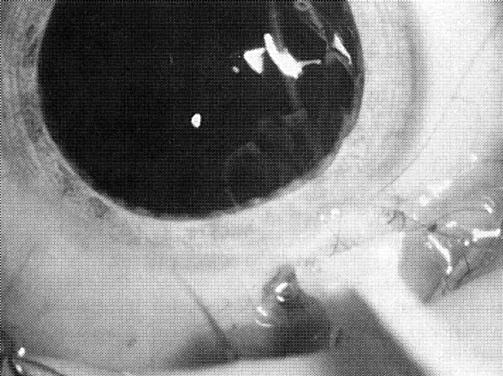

Type and Location

Usually, anterior polar cataracts are visually insignificant and allow normal visual development (see Fig. 1). However, some affect vision, and all require careful monitoring.7 Centrally located cataracts that are on or near the posterior lens capsule have a greater effect on the refraction of light and visual acuity (Fig. 2). Nuclear cataracts associated with metabolic disorders or prenatal infections produce double refracting systems that cause optical distortion and significantly decrease visual acuity (Fig. 3).

Fig. 2. A posterior subcapsular cataract that has reduced visual acuity in healthy illumination to 20/60.

Fig. 3. A nuclear cataract present in both eyes of a child with esotropia. The retinoscopy reflex was irregular, and cataract surgery was recommended. Metabolic evaluation and TORCH titer findings were negative.